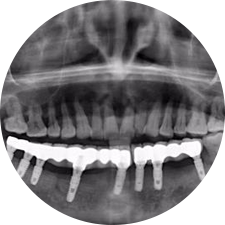

口腔種植是將人工牙根通過(guò)手術(shù)植入牙骨內(nèi),獲得牙槽骨牢固的支持,通過(guò)特殊的裝置和方式連接牙修復(fù)體,獲得與天然牙功能、結(jié)構(gòu)以及美觀相似的效果。

術(shù)前患者CBCT口掃1:1三維重建,模擬手術(shù)過(guò)程及預(yù)測(cè)術(shù)后治療效果,確定每顆植體植入的適合的種植位點(diǎn)、深度及角度,有效避免損傷頜骨重要解剖結(jié)構(gòu),提高手術(shù)準(zhǔn)確度與安全性。

惟德口腔種植體系是以患者感受為中心,取代傳統(tǒng)種植牙手術(shù)需要翻瓣、打孔、縫合,術(shù)前、術(shù)中、術(shù)后的繁復(fù)流程,采用3D導(dǎo)航微創(chuàng)準(zhǔn)確種植技術(shù),通過(guò)數(shù)字化CAD/CAM掃描技術(shù)獲得缺牙患者口腔數(shù)據(jù),以數(shù)據(jù)為基礎(chǔ)重建口腔模型進(jìn)行模擬種植。

術(shù)前將患者口內(nèi)的CBCT數(shù)據(jù)及咬合關(guān)系上傳到計(jì)算機(jī)中,建立1:1三維重建,模擬手術(shù)過(guò)程及預(yù)測(cè)術(shù)后治療效果,找出較佳種植位點(diǎn)、深度及角度,獲取實(shí)際種植體在頜骨內(nèi)的具體三維位置,有效避免損傷頜骨重要解剖結(jié)構(gòu),大大降低手術(shù)風(fēng)險(xiǎn),提升種植成功率。